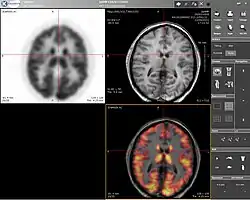

TEP-IRM

Scanner TEP-IRM

O TEP-IRM é a sigla de tomografia por emissão de positrões-imagem por ressonância magnética - em inglês: PET-MRI.

O TEP-IRM apareceu da reunião do exame imagiológico da medicina nuclear que utiliza radionuclídeos que emitem um positrão, no momento da sua desintegração, o qual é detectado para formar as imagens do exame, o TEP, e da IRM, a técnica que permite determinar propriedades de uma substância através do correlacionamento da energia absorvida contra a frequência, na faixa de megahertz (MHz) do espectromagnético, caracterizando-se como sendo uma espectroscopia [1].